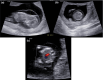

Methods: We used whole-exome sequencing in a consanguineous Turkish family with four siblings presenting with Pierre Robin sequence, arthrogryposis, heart malformation, splenomegaly, hydrocephaly, corpus callosum dysgenesis, brainstem, and cerebellar hypoplasia.

Results: We identified a novel homozygous pathogenic variant in exon 9 of COG6 (NM_020751.2): c.821del, p.(Arg274Lysfs*32). In this family, our post-mortem study led us to describe further the prenatal phenotype of CDG2L. In addition, it permits correlating the most relevant anomalies to a maldevelopmental cascade due to a neurodegenerative process of metabolic origin, affecting the entire central nervous system including the spinal cord.